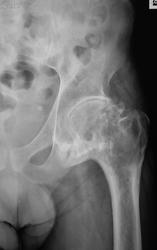

Исход Легг-кальве- пертеса в виде деф. артроза 3.

+1 за 3ю степень! У человека нога изуродована, а степень артроза влияет на группу инвалидности. Ну и как он будет с такой ногой работать?

Да, за артроз 3 стадии, и даже за 2 стадии, на мой взгляд, данных нет.

с кистовидной перестройкой. Анкилоз не вижу.

Пациент ранее был обследован МРТ, со слов пациента - виллезонодулярный синовит. Конечно понятно, что тут, не один синовит. Обследование было в платной клинике (три кабинетика приема) и на очень дорогом МРТ.